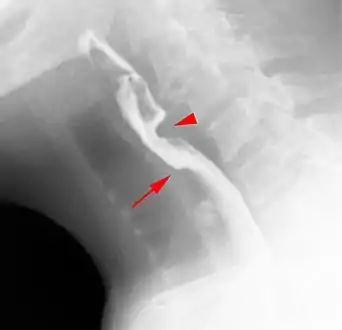

Esophageal web

Esophageal webs are thin membranes occurring anywhere along the esophagus.[1]

Esophageal webs are thin 2–3 mm (0.08–0.12 in) membranes of normal esophageal tissue consisting of mucosa and submucosa that can partially protrude/obstruct the esophagus. They can be congenital or acquired. Congenital webs commonly appear in the middle and inferior third of the esophagus, and they are more likely to be circumferential with a central or eccentric orifice. Acquired webs are much more common than congenital webs and typically appear in the cervical area (postcricoid).

The diagnostic test of choice is a barium swallow.